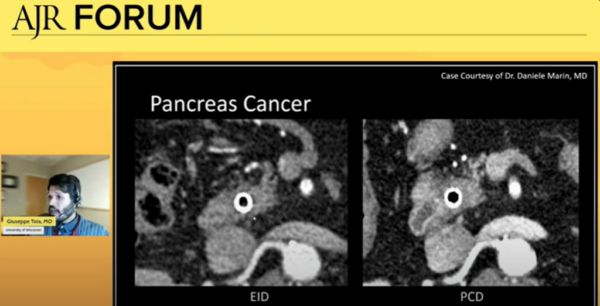

PCD-CT directly converts x-rays to electronic signal, allowing for substantial gains in spatial resolutions, contrast, noise reduction, and multienergy reconstruction. Previous CT technology uses energy-integrating detectors (EID-CT), following a two-step process of converting x-rays to light, then converting light to electronic signal.

During the panel, Dr. Toia illustrated clinical applications of PCD-CT for abdominal imaging. He highlighted its exciting potential to better monitor pancreas cancer and detect metastases in organs like the liver. He also shared that it’s beneficial in imaging the overall anatomy of the pancreas.